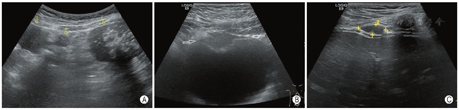

病例3,男,11岁5个月,因偶然发现腹部包块1个月余,在当地医院活检术后病理考虑促结缔组织增生性小圆细胞来院就诊。超声检查发现腹腔及盆腔肠系膜、大网膜、腹膜、膈肌、肝脏,肠壁、膀胱壁浆膜侧等处可见多发大小不等低回声包块,形态不规则、呈分叶状,较大病灶内多发砂砾样钙化灶,部分可见声影(图3),肠间隙有少量清亮腹腔积液。规律化疗后行手术切除,切除肉眼可见所有病灶,术后病理诊断促结缔组织增生性小圆细胞肿瘤,基因检测显示EWSR1基因断裂阴性。术后继续化疗并每隔1个月左右定期超声随访,术后2个月后超声显示膀胱壁复发病灶,目前仍在化疗中,肿瘤有所缩小。该病例发病至今随访时长共7个月。